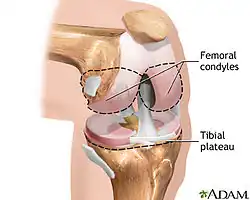

Knee

The knee joint joins the thigh with the leg and consists of the tibiofemoral articulation(one between the femur and tibia) and the patellofemoral articulation(one between the femur and patella)[4].

Table. Posterior Femoral Condyle Spherical Radius

| Normal knee | Varus knees | Valgus knees | |

|---|---|---|---|

| Medial condyle | 20.3 ± 3.4(16.1–28.0) | 21.2 ± 2.1(18.0–24.5) | 21.1 ± 2.0(17.84–24.1) |

| Lateral condyle | 19.0 ± 3.0(14.7–25.0) | 20.8 ± 2.1(17.5–30.0) | 21.1∗ ± 2.1(18.4–25.5) |

Source: Matsuda S., Miura H. Nagamine R., Mawatari T., Tokunaga M., Nabeyama R., and Iwamoto Y. Anatomical analysis of the femoral condyle in normal and osteoarthritic knees.J. Ortho. Res. 22: 104–109, 2004.